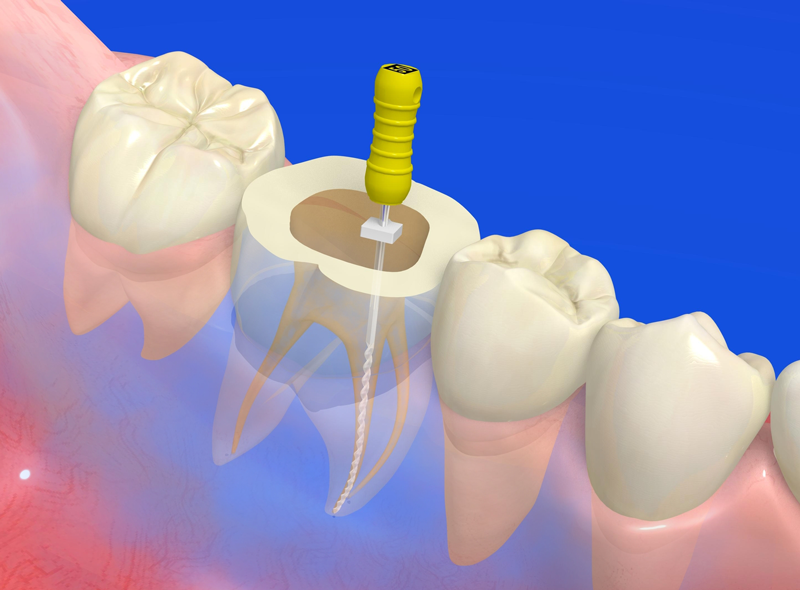

POINT治療の成功率を支えるニッケルチタンファイル・根管長測定器

従来のステンレス製ファイルは硬度が高いため、大きく湾曲していたり、狭くなっていたりする難易度の高い根管では、歯の組織を過剰に削ってしまうリスクがありました。

それに対し、当院で採用しているニッケルチタンファイルは、形状記憶特性と優れた柔軟性を併せ持ちます。この特性により、複雑な根管の形状に沿ってしなやかに進み、歯質へのダメージを最小限に抑えながら、根の先端隅々まで感染源を精密に除去することが可能です。

また、専用の根管拡大装置に装着して使用することで、治療の効率と精度が向上し、患者様の負担軽減や治療時間の短縮にも繋がります。